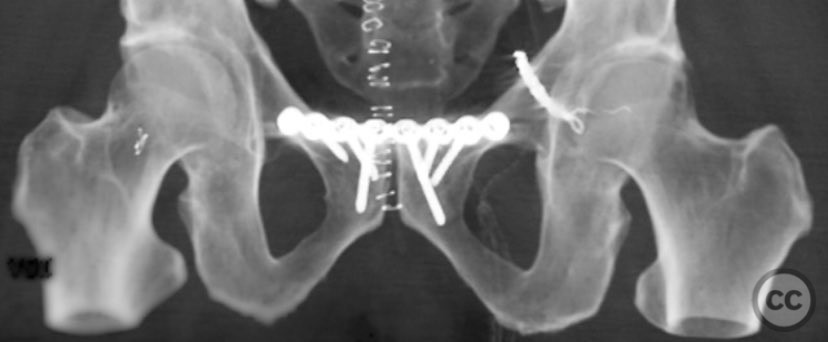

Clinical and radiological findings:  Middle-aged male involved in a motor vehicle accident sustained a complete symphysis pubis (SP) disruption and left sacroiliac (SI)/sacral combination fracture-dislocation (AO/OTA 61-C1.3). The patient presented with an open traumatic posterior pelvic wound. Initial assessment revealed hemodynamic instability requiring urgent laparotomy and subsequent angioembolization for pelvic hemorrhage. Axial CT imaging demonstrated significant displacement of the anterior and posterior pelvic ring, with embolic coils visible post-intervention.

Planning remarks:  The preoperative plan included staged fixation: initial supine positioning for low midline exposure and open reduction internal fixation (ORIF) of the pubic symphysis, followed by prone repositioning for irrigation and debridement (I&D) of the open posterior wound and stabilization of the posterior pelvic ring via iliosacral screw fixation under fluoroscopic guidance.

Patient positioning:  The patient was first positioned supine for anterior pelvic exposure and fixation, then repositioned prone for posterior wound management and fixation.

Anatomical surgical approach:  Anteriorly, a low midline infraumbilical incision was made to expose the symphysis pubis, with subperiosteal dissection of the rectus sheath and direct visualization of the disrupted symphysis. Posteriorly, a longitudinal midline approach over the sacrum was utilized, incorporating the traumatic wound for I&D. Deep dissection allowed access to the sacral ala and SI joint. A tenaculum clamp was applied percutaneously to achieve reduction of the sacral/SI fracture-dislocation. Iliosacral screws were inserted percutaneously under fluoroscopic control across the SI joint into S1.

The sequence of anterior then posterior fixation allowed unimpeded access to both injury sites. The use of a tenaculum clamp facilitated reduction of the complex posterior injury. No technical interference was encountered between anterior plate fixation and subsequent posterior iliosacral screw placement. The presence of embolic coils did not impede surgical access or reduction maneuvers.

Orthopaedic implants used:   3.5 mm anterior symphyseal plate, cannulated iliosacral screws